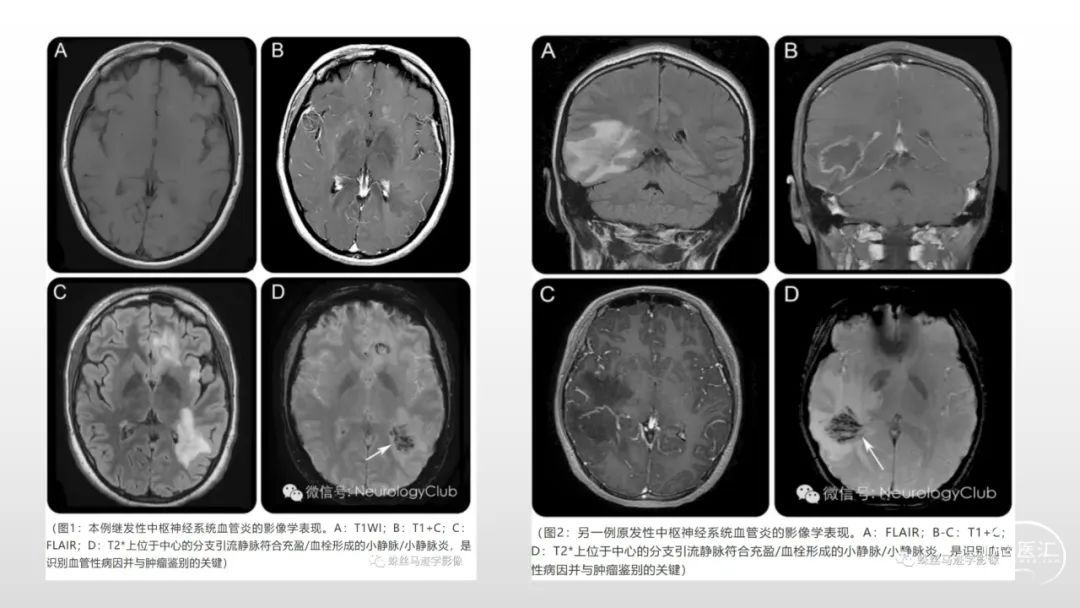

颅脑影像诊断基础知识讲座:感染和免疫性疾病2